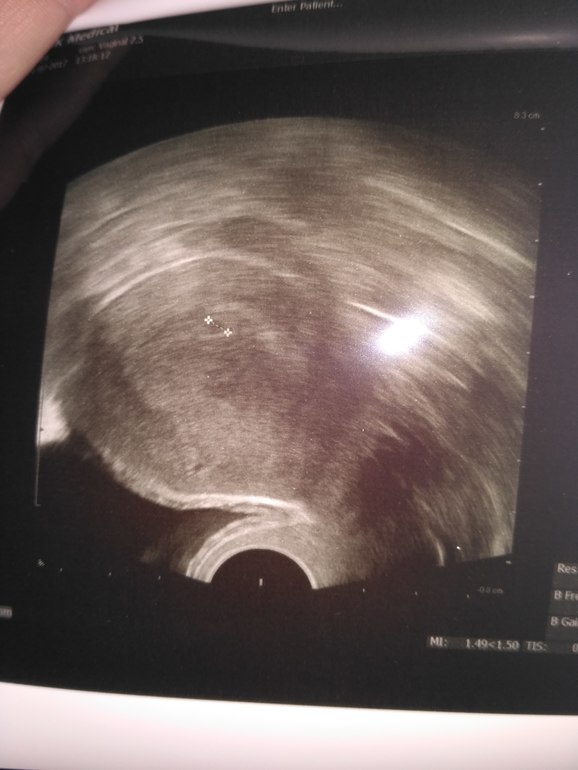

Анализы и процедуры. Помощь в расшифровке результатовВсем привет! У меня сегодня 19 ДПП, РЕ решила сделать УЗИ. Сначала водила по животику и сказала что она видит 2 ПЯ (была подсадка двух АА+АВ), куда подсаживали там и сидят, но один большой, а другой маленький (размеры не знаю). Решила сделать УЗИ вагинального, но там увидела только 1. В заключение РЕ написала одного... И сказала ждать УЗИ на СБ, возможно там появятся два сердечка... У кого такое было? Забилось два? Или одно?